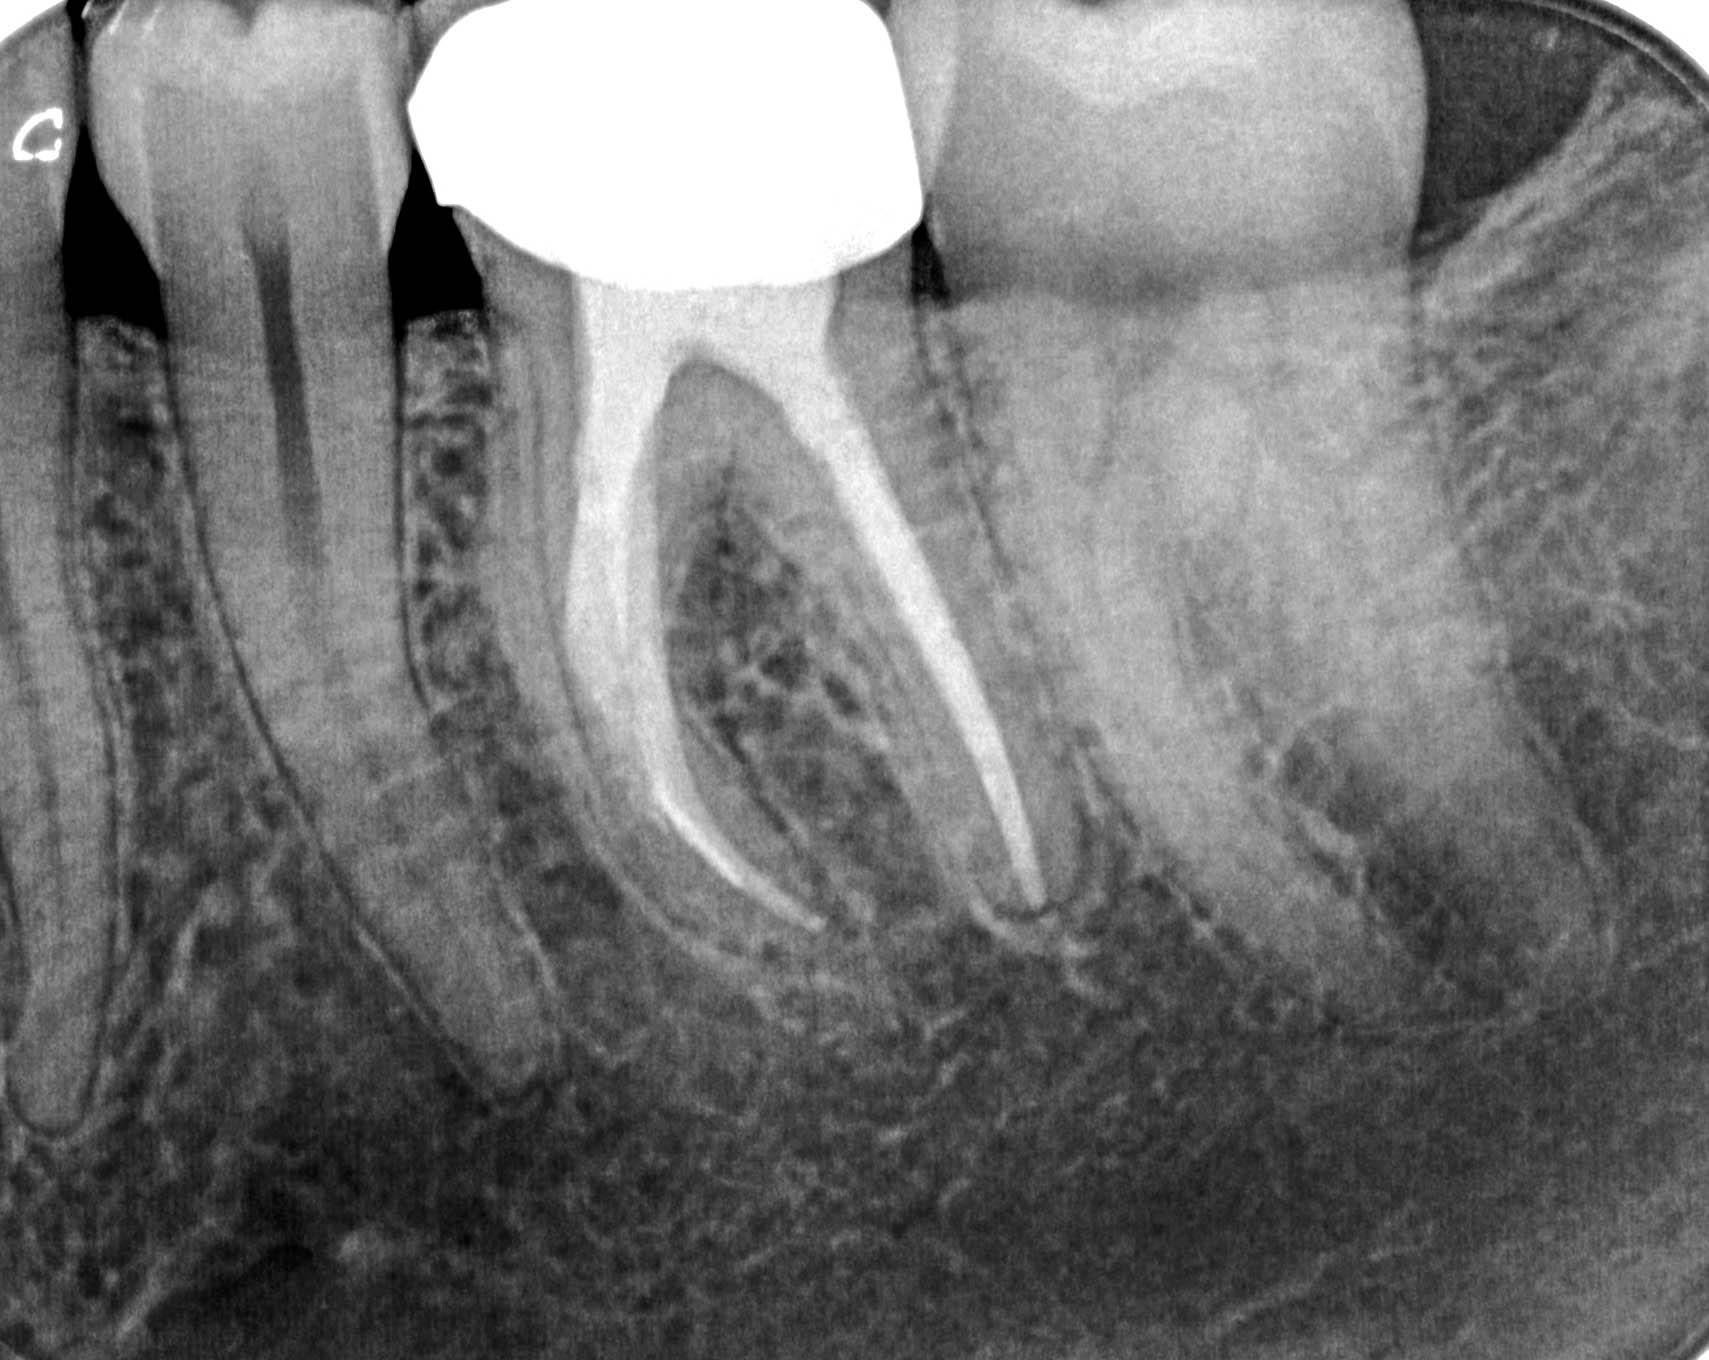

09.12.2015 Veröffentlicht 14. März 2016 am 1709 × 1360 in Calciumhydroxid – Überpressung (1) 09.12.2015